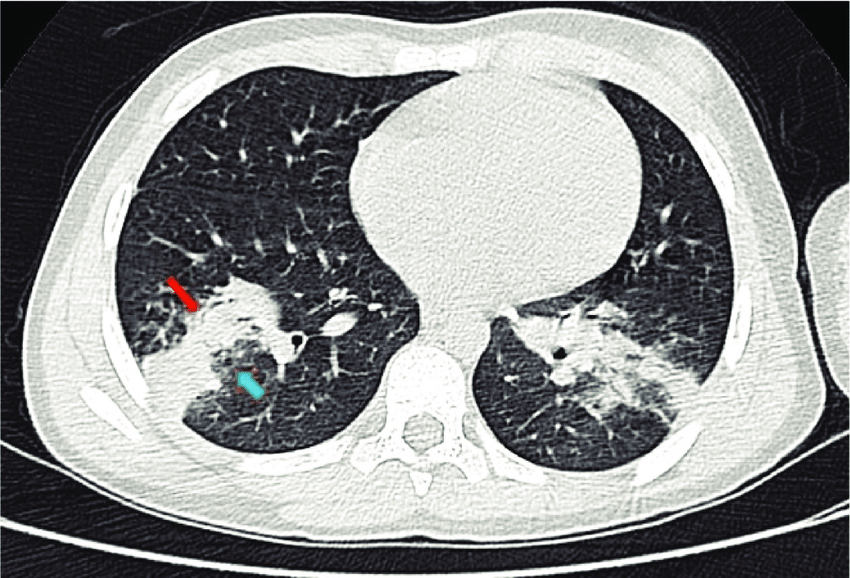

低線量肺CT診断画像1

低線量肺CT診断画像2

低線量肺CT診断画像3

低線量肺CT検査

低線量肺CT検査は、通常のCT検査よりも少ない放射線量で肺の状態を詳しく調べる検査です。

胸部X線検査よりも小さな病変の発見に優れており、肺がんの早期発見に役立ちます。

この検査でわかること

• 肺がんの疑い

• 慢性閉塞性肺疾患(COPD)などの肺の病気

• 肺の結節影などの所見

• 肺の炎症や過去の病変の痕跡